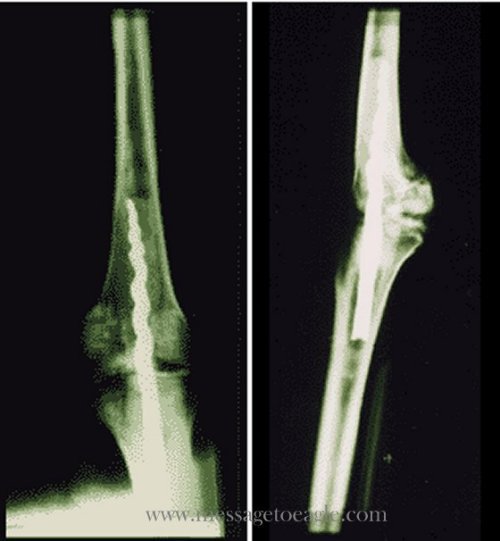

Hình ảnh X-quang cho thấy chiếc ốc vít dài trong chân của xác ướp. (Ảnh: messagetoeagle.com)

Một ốc vít kim loại 9 inch được tìm thấy trong xác ướp 2.600 năm tuổi trong chân của một vị linh mục Ai Cập tên là Usermontu đã gây chấn động trong giới khoa học toàn thế giới.

Năm 1996. Giáo sư Wilfred Griggs, nhà Ai Cập học tại Đại học Brigham Young đang thực hiện nghiên cứu về DNA xác ướp trong 6 xác ướp nằm tại Bảo tàng San Jose Rosicrucian, bỗng phát hiện thấy tia X hiển lộ ra một ốc vít kim loại ở gần xương bánh chè của Usermontu.

Xác ướp cho thấy bằng chứng của một ca phẫu thuật tiên tiến đã được thực hiện cách đây 2.600 năm. Nhóm nghiên cứu vô cùng kinh ngạc khi thấy chiếc đinh ghim đã được tạo ra với nguyên tắc cơ sinh học hiện đại ngày nay nhằm cố định xương.

Giáo sư Griggs cho biết: “Đây là bằng chứng cho chúng ta thấy người cổ đại thực sự đã rất phát triển. Đôi khi sự tự mãn về nền văn hóa ngày nay của nhân loại đã cản trở đánh giá đúng đắn về con người từ các nền văn hóa và thời đại khác nhau, những người có khả năng suy nghĩ và hành động tuyệt vời đến khó tin”.